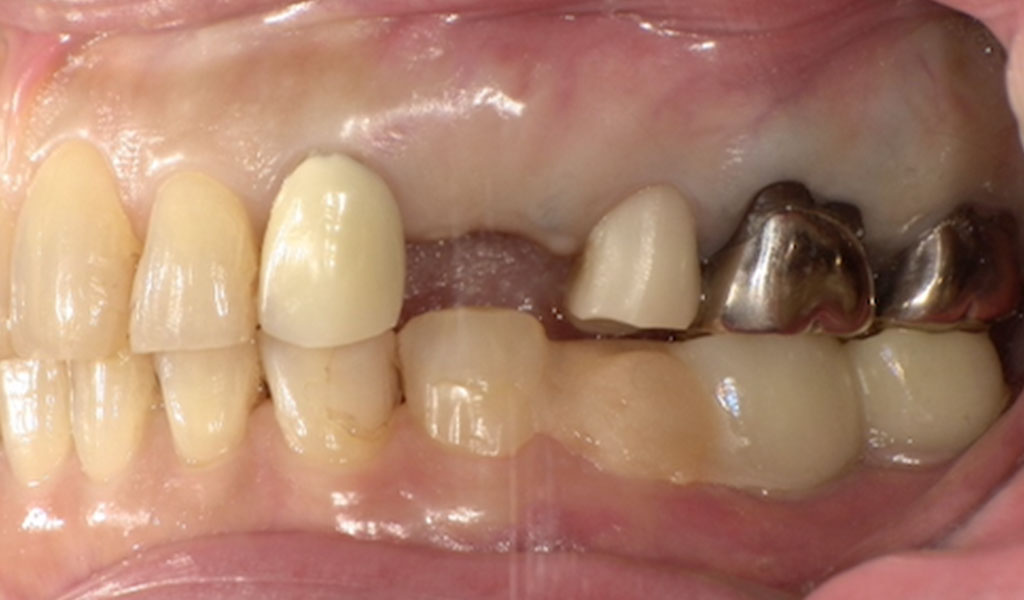

Before(左上4番)